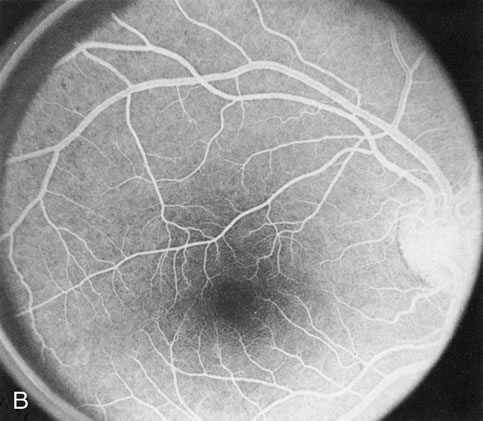

Fundus albipunctatus typically shows multiple, small white dots, which are deep in the retina, regular, and monotonous in their similar size, shape, and color and which involve the entire posterior pole into the equator while sparing the macula (Fig. 3A). These multiple dots are not apparent on FA. There may be a mottling of the background choroidal fluorescence and small areas of irregular transmission hyperfluorescence (especially surrounding the macula), but neither of these findings corresponds to the observed white dots8,9 (Fig. 3B).